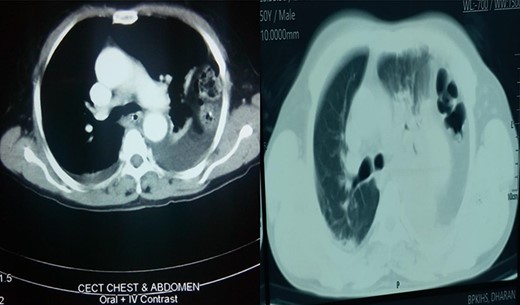

A retrospective analysis was carried out to review records of patients who presented to our department over a period of 3 years from December 2017 to January 2020. All patients with diaphragmatic hernias were included in the study. Preoperative diagnosis of diaphragmatic hernia was based on history, clinical examination and radiological investigations (chest X-ray and CT) (Figs 1 and 2).

X-ray chest showing collapsed left lung with herniated bowel loops in left thoracic cavity.

Axial section showing collapsed left lung with bowel in left thoracic cavity.